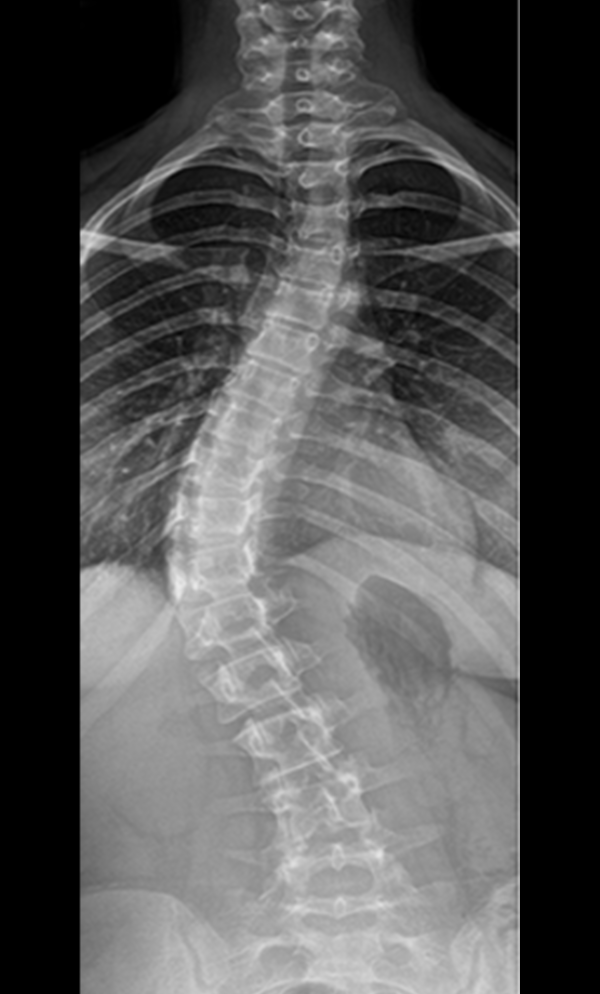

Gallery : Before - After

• Scoliosis surgery with small incisions using flexible correction technology (VBT) and growth-preserving techniques such as remotely controlled magnetic growing rods

• Scoliosis for children and adults